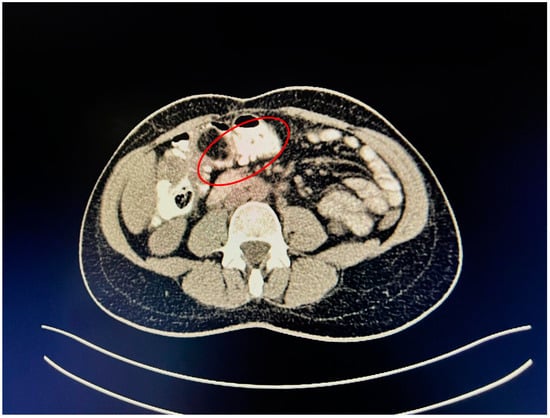

A contrast-enhanced computed tomography (CT) scan conducted on the day of admission revealed circumferential parietal thickening of a maximum of 21 mm at the hepatic flexure of the colon. This thickening extended over a length of approximately 45 mm, resulting in filiform, axial stenosis of the lumen, without any overlying distension of the colonic frame. The parietal thickening was moderately iodophilic and accompanied by discrete linear-type densification of locoregional fat, which was most likely a desmoplastic reaction. A tumor formation with a maximum axial diameter of approximately 29/28 mm, extending craniocaudal on a length of approximately 27 mm, was located at the distal end of the parietal ingrowth with an intraluminal site. This tumor formation had a polycyclic contour, thin septa within, and a discrete lodophilic peripheral appearance. It appeared to have a wide base of implantation at the level of the postero-inferior wall of the colon; mild hepatomegaly in the liver, with a homogeneous structure and a regular surface, and the absence of focal primary or secondary lesions; adenopathies in the hepatic hilum with a maximum diameter of 16/12.5 mm and in the celio-mezenteric territory with a maximum diameter of 24/19 mm; microadenopathies with the gastro-hepatic ligament; and an absence of subdiaphragmatic fluid (Figure 1, Figure 2 and Figure 3).

Figure 3. Mass resulting in filiform axial narrowing of the lumen without associated distention of the colon.